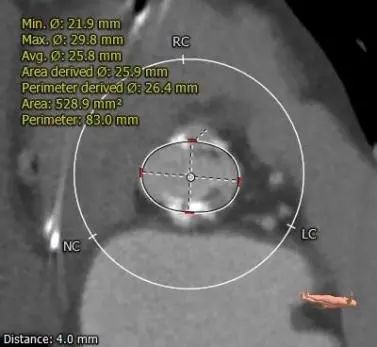

主动脉根部测量

1.Type 0 型二叶瓣,瓣叶增厚,双侧瓣叶边缘连续条状钙化,瓣膜锚定难度适中,瓣膜植入受两侧钙化挤压存在移位风险及瓣周漏风险。

2.冠脉开口高度可,未见冗长瓣叶,结合瓦氏窦、STJ内径综合预估,冠脉风险适中。

3.推荐22mm球囊预扩,根据球扩后腰征决定AV26还是AV29瓣膜,瓣环下2mm定位释放,建议释放后调整至右前斜足位 RAO 6 CRA 35 左右进一步确定人工瓣膜展开形态。